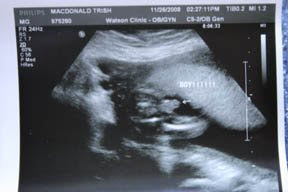

We had our 20-week sonogram the day before Thanksgiving. No surprises there, but the fact that we decided to find out what we are having while I was laying on the table was a surprise to us and everyone else! We are proud to announce that our newest blessing is a little boy!

This is the first time we have found out the gender of our baby ahead of time, and it has been fun so far knowing. I have to wonder if I am more excited that I know or more excited that we are having a boy like I wanted :) The older two kids were with us at the appointment. Caleb was thrilled to find out he was having a baby brother (which he has been saying all along) but Ella reacted a little differently. She really wanted a little sister, but after we talked to her about it for a little while her attitude changed and she was somewhat happier.